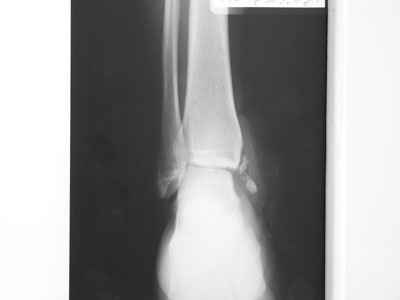

Re: Остеомиелит медиальной лодыжки

Нашел в архиве форума снимки от 2007 года. Классная штука интернет! Александру Николаевичу отдельное спасибо!